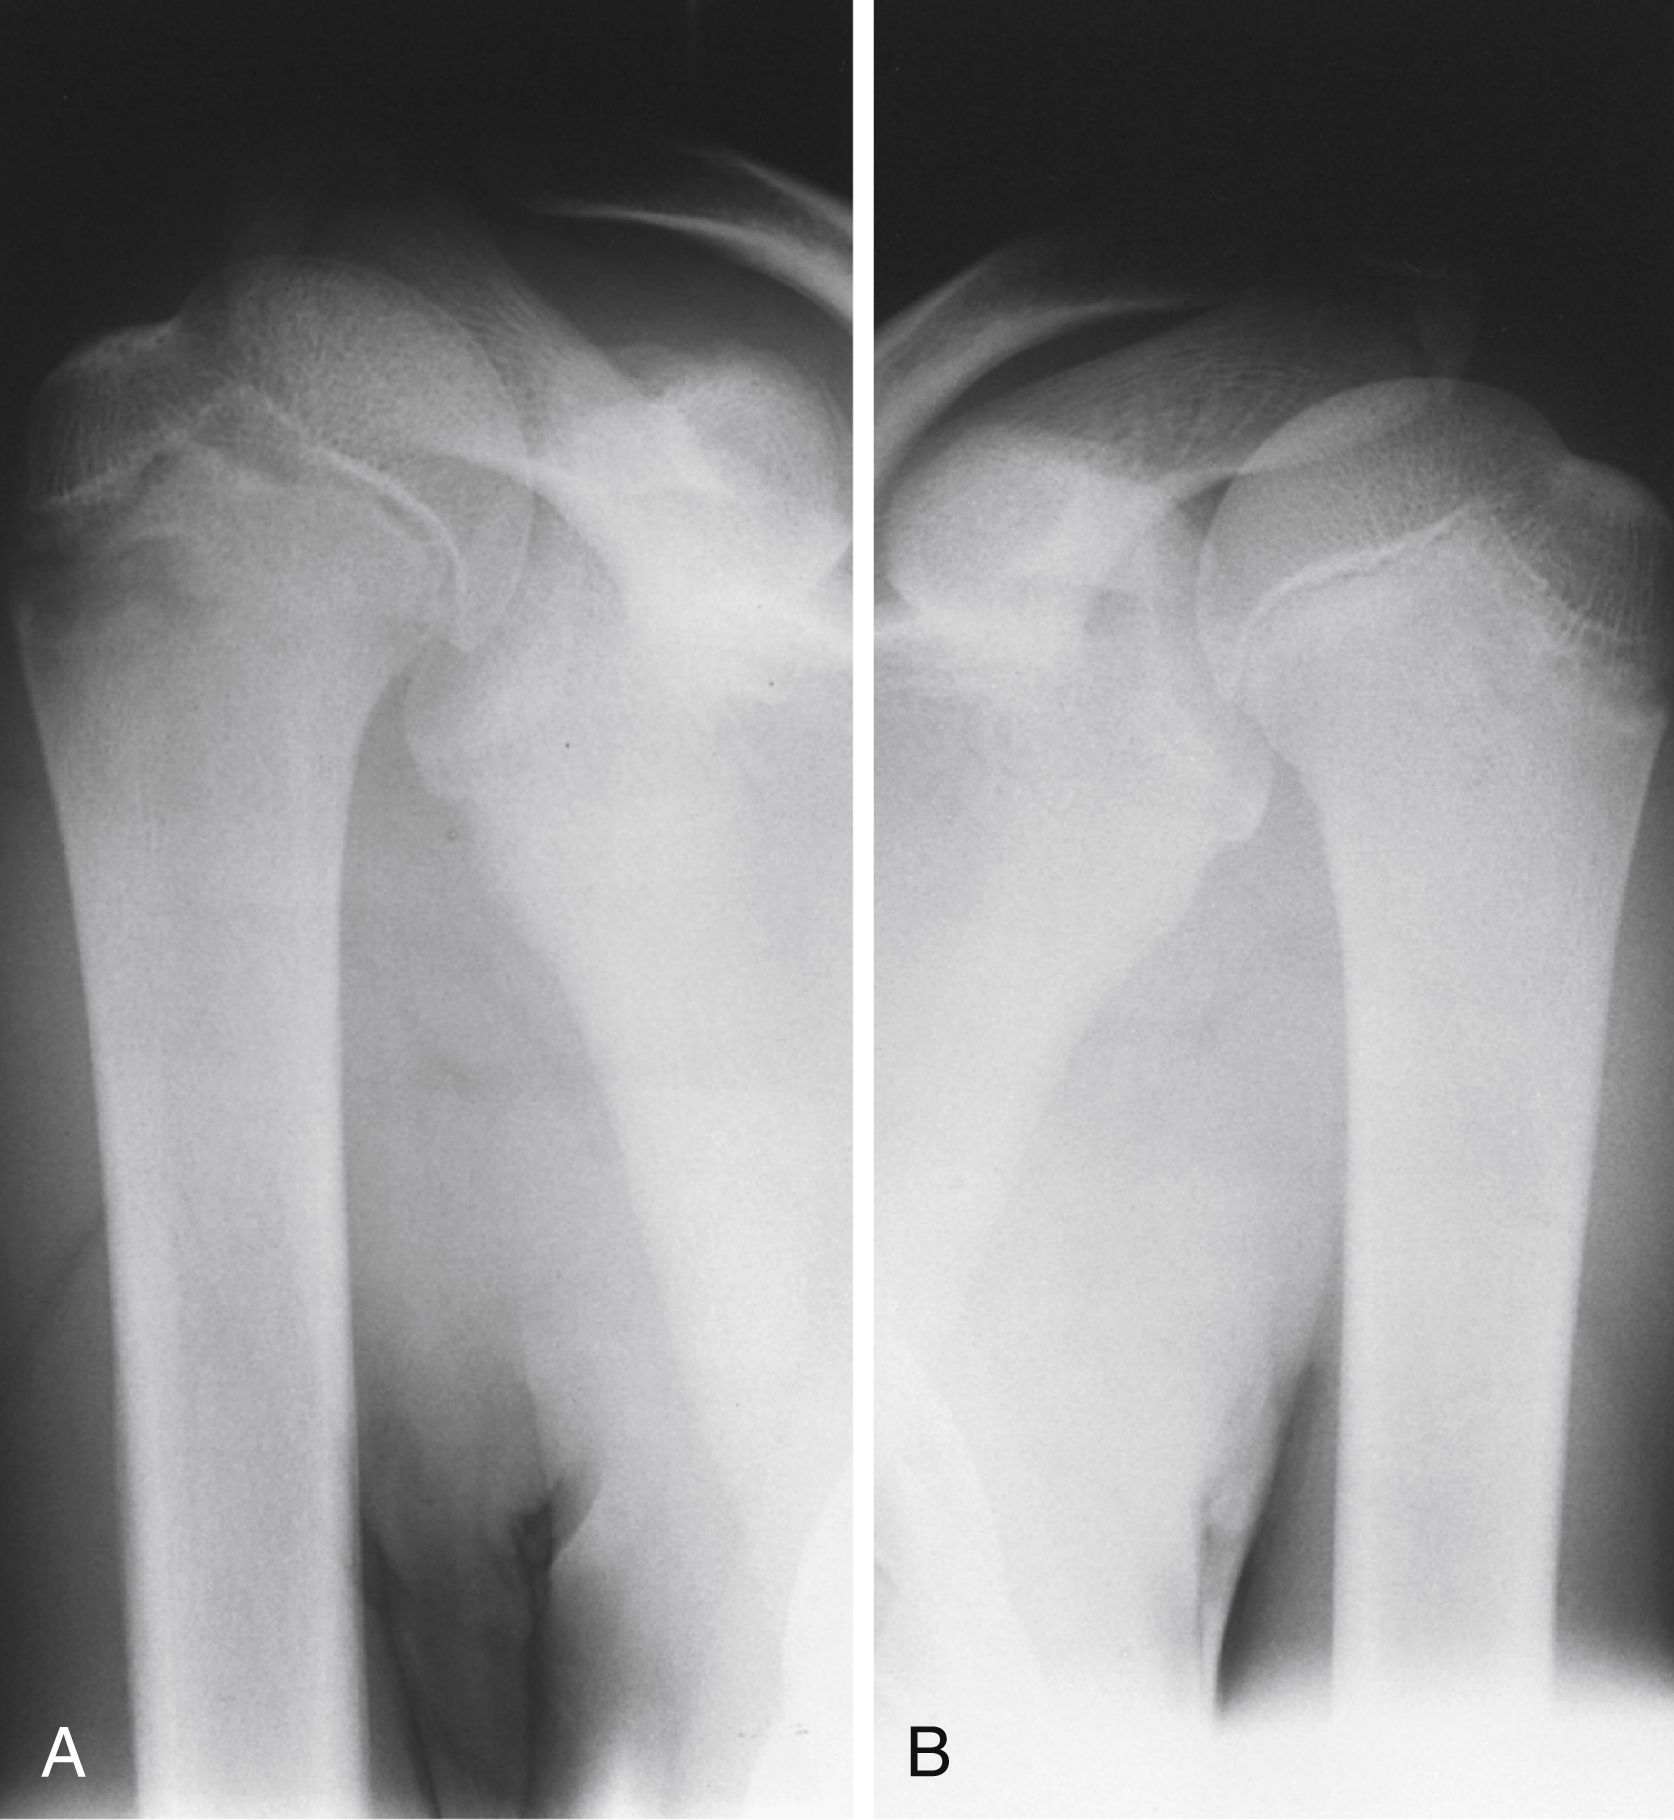

Fractures of the proximal humerus separate along old epiphyseal lines, producing four distinct segments consisting of the articular surface (anatomic neck), greater tuberosity, lesser tuberosity, and humeral shaft (surgical neck). The Neer classification system is based on the relationship of these fracture fragments. In this system, a segment is considered displaced if it is angled more than 45 degrees or separated more than 1 cm from the neighboring segment. Because this classification system considers only displacement, the number of fracture lines is irrelevant. There are four major categories of fracture: (1) minimal displacement ( Fig. 45.12 ), (2) two-part displacement ( Fig. 45.13 ), (3) three-part displacement, and (4) four-part displacement. When present, anterior and posterior dislocations are included as part of the classification. Impaction and head-splitting fractures are classified separately.

Three-part minimally displaced fracture of the proximal humerus involving the greater and lesser tuberosities.

Anteroposterior (A) and axillary (B) radiographic views of a two-part displaced fracture of the proximal humerus. The degree of displacement often is better visualized on the axillary view.

Courtesy David Nelson, MD.